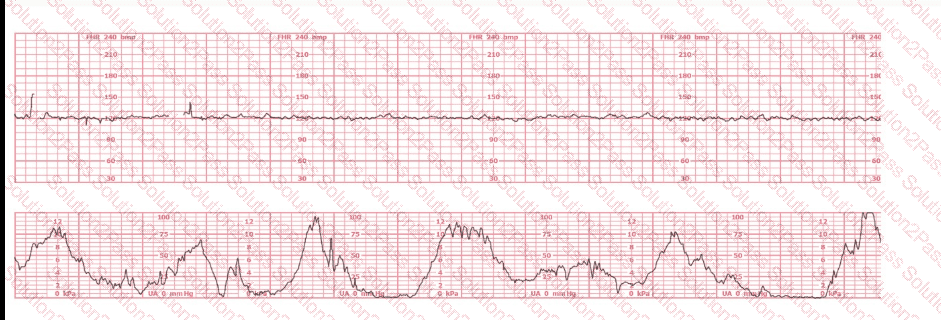

The pattern on the fetal heart rate tracing shown is likely due to

The fetal heart rate tracing shown demonstrates:

The tracing shown is a:

The most probable underlying fetal physiologic cause for this tracing would be:

The fetal heart rate tracing shown is obtained upon the woman's admission to labor and delivery. This tracing is most consistent with what maternal condition?